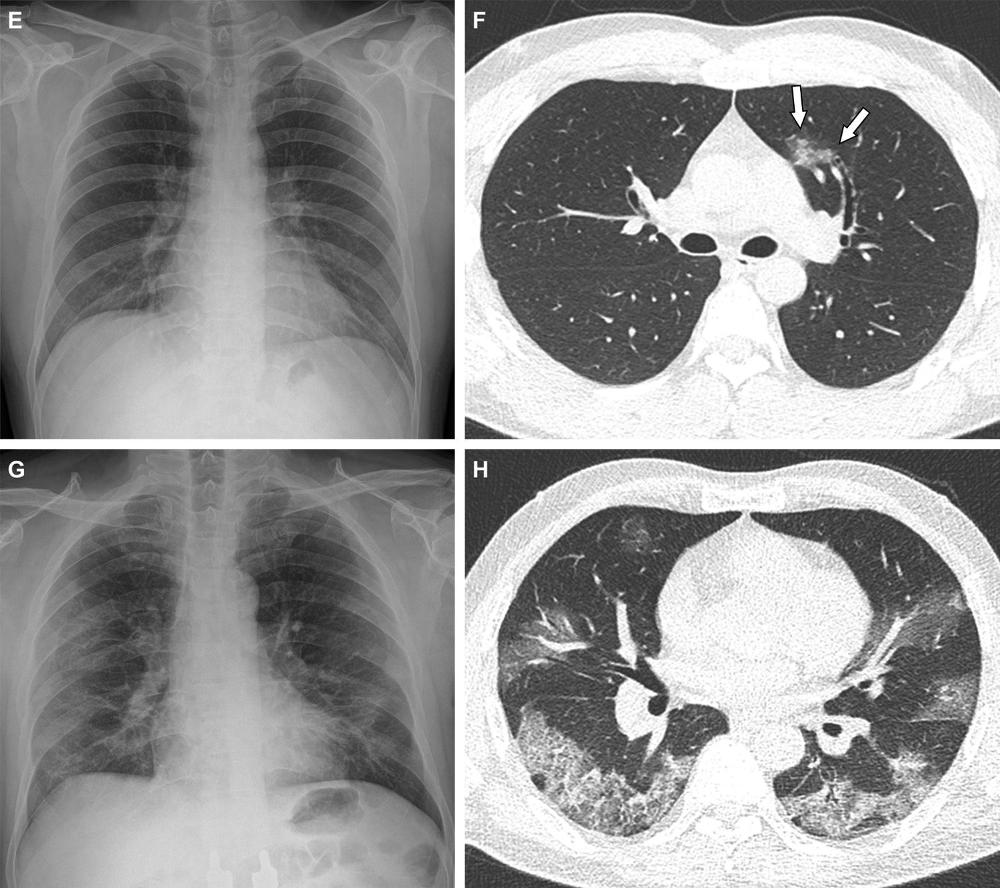

Figure 2. Representative cases showing pneumonia extents and patterns on chest X-ray (CXR) and CT images. (A and B) A 65-year-old female with breakthrough infection 2 months after a second dose of the Pfizer vaccine (fully vaccinated). The patient had a history of hypertension. (A) CXR obtained at admission showing no abnormal opacification in both lung zones. The CXR extent of pneumonia was scored as 0 (no evidence of pneumonia). (B) Axial chest CT image at the lower lobe level (obtained on the same day) showing negatively for pneumonia; CT extent of pneumonia was scored as 0 (no evidence of pneumonia). (C and D) A 48-year-old male with 1 month after a first dose of the AstraZeneca vaccine (partially vaccinated). The patient had no history of comorbidity. (C) CXR obtained at admission showing no abnormal opacification in both lung zones. The CXR extent of pneumonia was scored as 0 (no evidence of pneumonia). (D) Axial chest CT image obtained on the same day showing unilateral ground-glass opacity with a non-rounded morphology in the left lower lobe (arrows). CT extent of pneumonia was scored as 1 (1-25% involvement) and this case was classified as indeterminate appearance of COVID-19 according to the RSNA chest CT classification system.